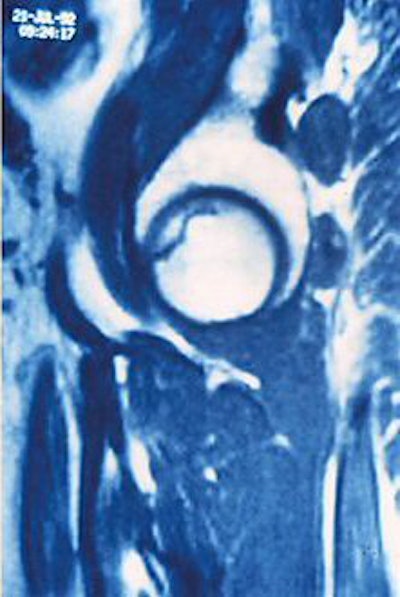

![]() |

| Right femoral head of 24-year-old woman who received high-dose steroid therapy for systemic lupus erythematosus. Coronal T1-weighted MR image (A) obtained 10 weeks after initiation of therapy shows band-like hypointense zone. Coronal STIR image shows matching hyperintense zones (B). Iida S, Harada Y, Shimizu K, Sakamoto M, Ikenoue S, Akita T, Kitahara H, Moriya H, "Correlation Between Bone Marrow Edema and Collapse of the Femoral Head," (AJR 2000; 174: 735-743). |

According to the results, 28% of the 46 hips had diffuse signal abnormalities in the marrow of the femoral head and neck. On T1-weighted images, these regions were ill-defined and decreased in signal intensity; on STIR images, they were diffusely hyperintense indicating bone marrow edema.

"Bone marrow edema was found in the living bone outside the band-like hypointense zone on the initial MR," the group stated. "At the time bone marrow edema was detectable on MR imaging, all 13 hips were symptomatic."

At final examination, 85% of these cases had progressed to advanced osteonecrosis, and bone marrow edema was highly correlated with the subsequent collapse of the femoral head.